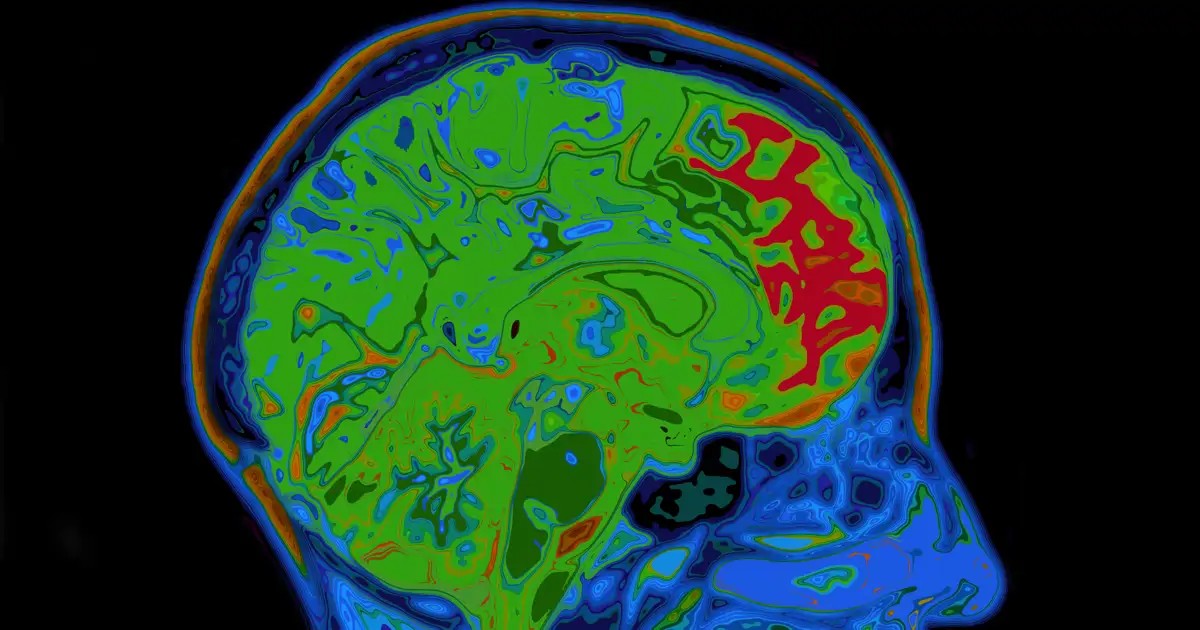

Proč se někteří lidé chtějí po dlouhém a stresujícím pracovním dni sejít na pivo? Nebo proč si po kávě zapálí cigaretu? Tyto návyky, které jsou zdravotně škodlivé, aktivují odměnový systém v mozku. Tento komplexní mechanismus byl rozluštěn týmem výzkumníků z Lékařského centra Georgetownské univerzity a je zmiňován v článku publikovaném v časopise Nature Communications.

Během výzkumu vědci identifikovali neurobiologický mechanismus, který výrazně ovlivňuje rychlost, s jakou mozek vytváří asociace odměny. Toto ovlivňuje nejen vznik prospěšných návyků, ale i rozvoj závislostí. Konkrétně se jedná o protein KCC2, který funguje jako katalyzátor asociativního učení a v článku je přirovnáván k vypínači.

KCC2 je nezbytný protein pro homeostázu neuronálního chloridu, který navíc moduluje aktivitu neuronů odpovědných za vylučování dopaminu, neurotransmiteru štěstí. Snížení aktivity tohoto proteinu vede k zásadnímu nárůstu aktivity dopaminergních neuronů, což rychle zesiluje nové asociace mezi environmentálními podněty a uspokojivými výsledky.

Tým výzkumníků pozoroval v mozkovém tkáni myší a prostřednictvím behaviorálních experimentů zjistil, že vztah je nepřímo úměrný: čím nižší je přítomnost KCC2, tím vyšší je citlivost na učení. Dále zjistili, že tento protein reguluje nejen frekvenci aktivace, ale také koordinaci neuronů. To je klíčové, protože synchronizovaná aktivita nervových buněk zvyšuje sekreci dopaminu.